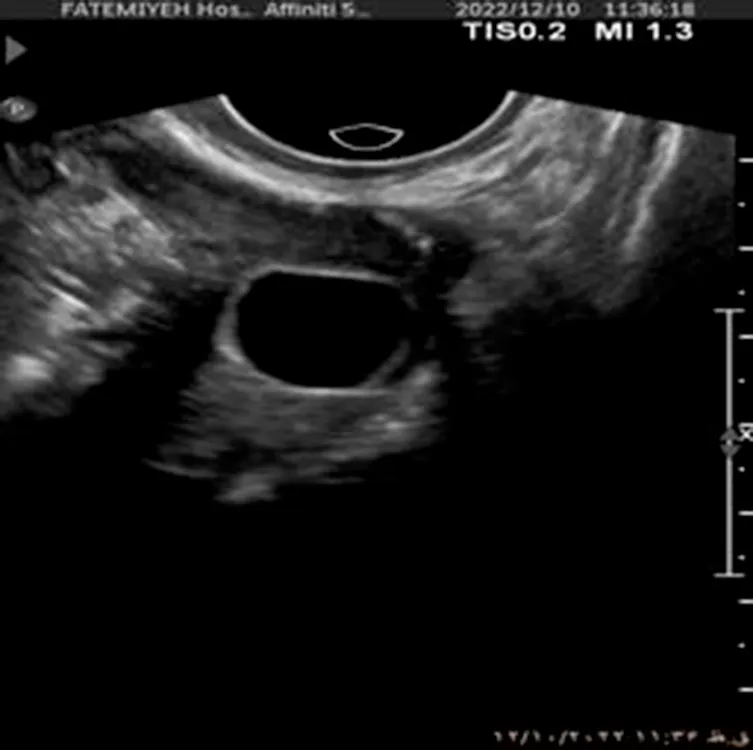

The dataset used in this study was collected from Fatemieh Hospital of Hamedan University of Medical Science during the years 2023 and 2024. It consists of ultrasound images, each with a resolution of 1,024 × 1,024 pixels, capturing various ovarian conditions. The dataset is organized into three distinct classes: Normal, Dominant Follicle, and Polycystic Ovary Syndrome (PCO). These classes represent crucial clinical states requiring different management approaches, with Normal indicating healthy ovarian function, Dominant Follicle associated with ovulatory cycles, and PCOS characterized by the presence of multiple small cysts, a key feature of polycystic ovary syndrome.

To provide further context, the dataset consists of 301 transvaginal ultrasound images, each corresponding to a unique patient, resulting in a total of 301 women aged between 20 and 45 years. All ultrasound scans were performed using a Philips Affiniti 50 system (Philips, Netherlands). To ensure consistency and clinical accuracy, all images were captured by a single board-certified obstetrician-gynecologist with fellowship training in infertility.

The dataset includes a total of 301 labeled ultrasound images, as shown in Table 1, with 41 images classified as Normal, 144 as Dominant Follicle, and 116 as PCO. The labeling was performed by experienced radiologists, ensuring high-quality ground truth for model training and evaluation.

Additionally, Figure 1 below presents a sample of ultrasound images from each of the three classes, demonstrating the visual differences between the conditions and the challenges involved in classification.

Figure 1

www.frontiersin.org

Figure 1. Sample ultrasound images from the dataset, representing the three classes: (a) Normal, (b) Dominant Follicle, and (c) Polycystic Ovary Syndrome (PCO). These examples highlight the visual differences between the classes used for muticlass classification.